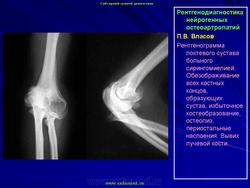

КСС. Артропатия. Сирингомиелия. +

Артропатия.  Сирингомиелия.